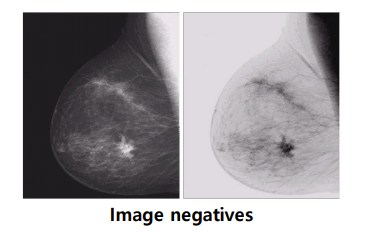

Image Negative(음화)

이미지의 양과 음을 바꾸는 영상 처리 기법. 위 사진처럼 오른쪽 사진이 사람이 인식하기에 더 대조가 잘 됨을 확인 가능.